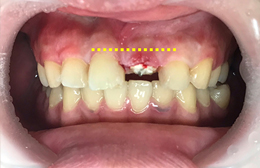

根っこ(歯根)が歯茎の中にあり、このままでは差し歯に出来ない状態です。

歯茎を隣の歯と合わせ審美的な点からも治療し、差し歯に出来るようにしました。